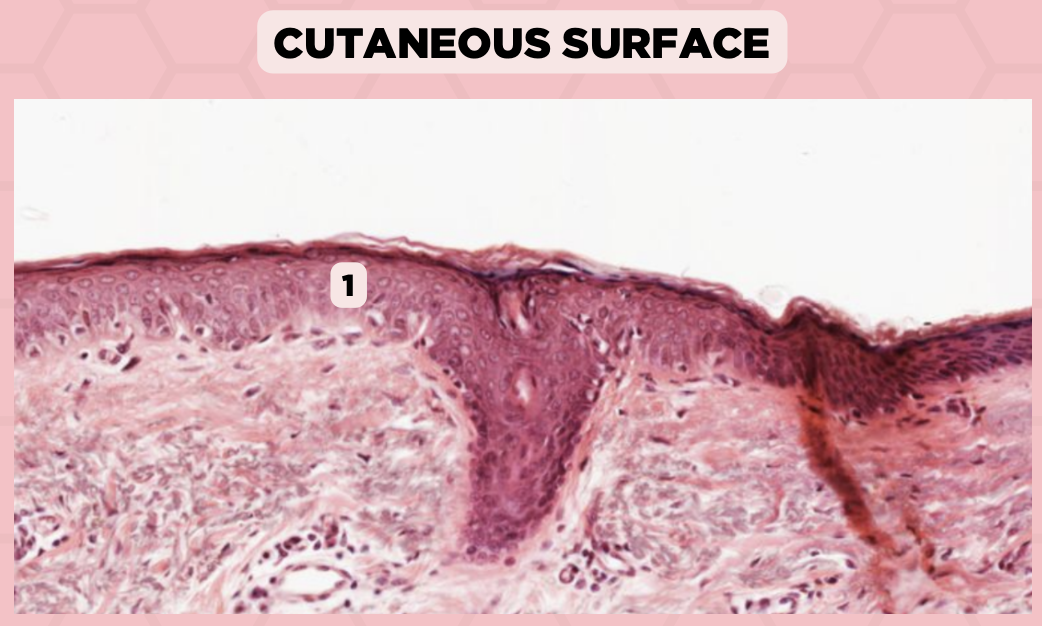

Lip

What specimen is being showed in this picture?

d. Mucosa/Mucous Membrane

Identify the structure labelled in the given image?

a. Epidermis

b. Dermis

c. Hypodermis

d. Mucosa/Mucous Membrane

b. Nonkeratinized stratified squamous epithelium

Identify the structure’s lining epithelium given in the image?

a. Keratinized stratified squamous epithelium

b. Nonkeratinized stratified squamous epithelium

Lip

What specimen is being showed in the picture?

Non-Keratinized Stratified Squamous Epithelium (Mucosa/Mucous Membrane)

Identify the structure labeled as 1.